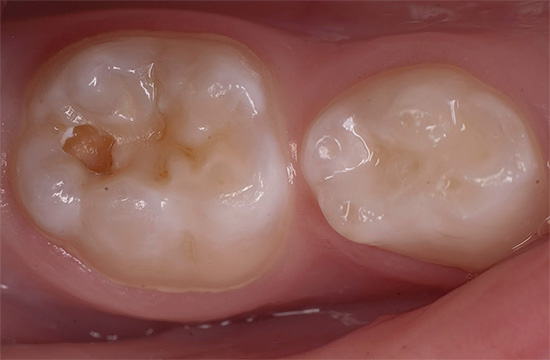

La carie dentale è accompagnata da una violazione dell'integrità del dente con la formazione di una cavità. Tuttavia, non pensare che un foro sarà necessariamente visibile nel tuo dente: spesso una cavità cariata non viene visualizzata e può essere trovata solo all'appuntamento del dentista quando si sonda un dente con uno strumento speciale per diagnosticare la carie.

Tuttavia, ci sono casi abbastanza comuni in cui il paziente stesso vede una formazione di cavità nel dente, poiché con la carie della dentina il quadro clinico è piuttosto ricco di sintomi associati. Questi includono:

- Disagio da masticare

- Mal di denti da irritanti della temperatura (cibi freddi, caldi o bevande), dolci;

- Imperfezione estetica, soprattutto quando il dente anteriore inizia a decadere.

Un sintomo del dolore può verificarsi da una o più sostanze irritanti contemporaneamente, ma scompare rapidamente dopo aver eliminato la fonte di irritazione.

A volte la carie della dentina non si manifesta in alcun modo, ma solo pochi sono così fortunati. La maggior parte delle persone con la comparsa di almeno uno o più dei suddetti sintomi sono già pronte a fissare un appuntamento con un dentista, in modo da non ritardare o aggravare il processo.